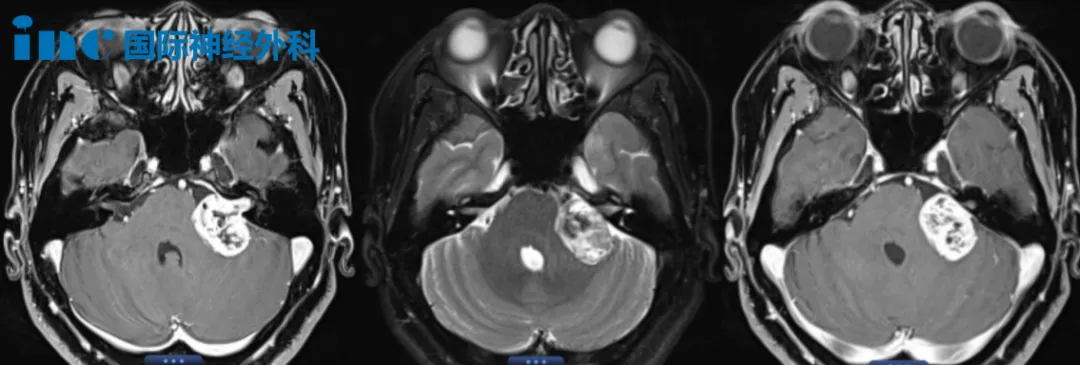

52岁女性-左侧较大听神经瘤

52岁的江女士,较大的听神经瘤已经压迫面听神经及小脑。头晕、步态不稳、左侧耳疼、耳鸣、听力下降等严重症状严重影响到她的生活和工作。手术风险较大,这一次终于等到巴教授。江女士相信强强联合,定会为她解决困境。面对巴教授的鼓励,她举起拳头,铿锵有力地说:“加油!加油!”而丈夫也一直在旁边温柔的抚着她的肩膀,给她力量。对于江女士关心的面瘫问题,术前谈话中,巴教授也为她再次详细解答。

3岁男孩-脑干占位性病变

“握拳,用力握”,巴教授握住3岁脑干占位性病变患者浩浩的小手,仔细检查着浩浩的术前状况后,向浩浩妈妈解释相关手术方案。浩浩乖巧的坐在病床上,大大的眼睛充满了好奇,“他是不是明天就要帮我做手术的?”

对于妈妈依赖的浩浩,不停地喊:“妈妈,妈妈!”当妈妈抱起他时,他像一个快乐的小鸟,摆摆小手,晃着腿,和妈妈贴贴。如此可爱的浩浩实在是父母的心头肉,然而多地寻医,医生都表示脑干手术难度很大,术后可能会有偏瘫的风险。得知巴教授来华消息后,尽快联系了INC,咨询当天他们就决定咨询了这次巴教授天坛医院手术交流机会。